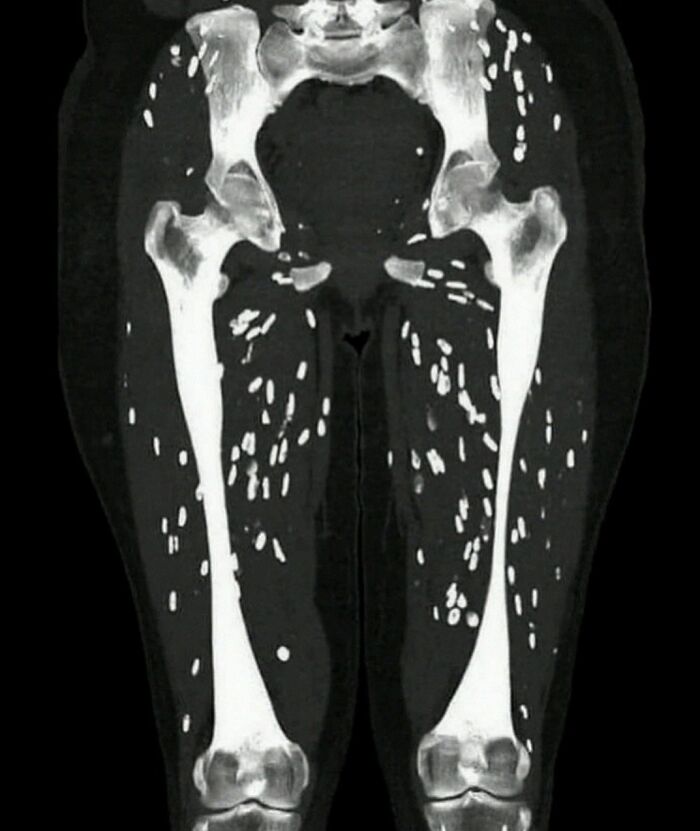

Patient presents with muscle weakness and pain

It's called muscular cysticercosis. Those are from tapeworm larvae in the muscle tissue. 😫😫